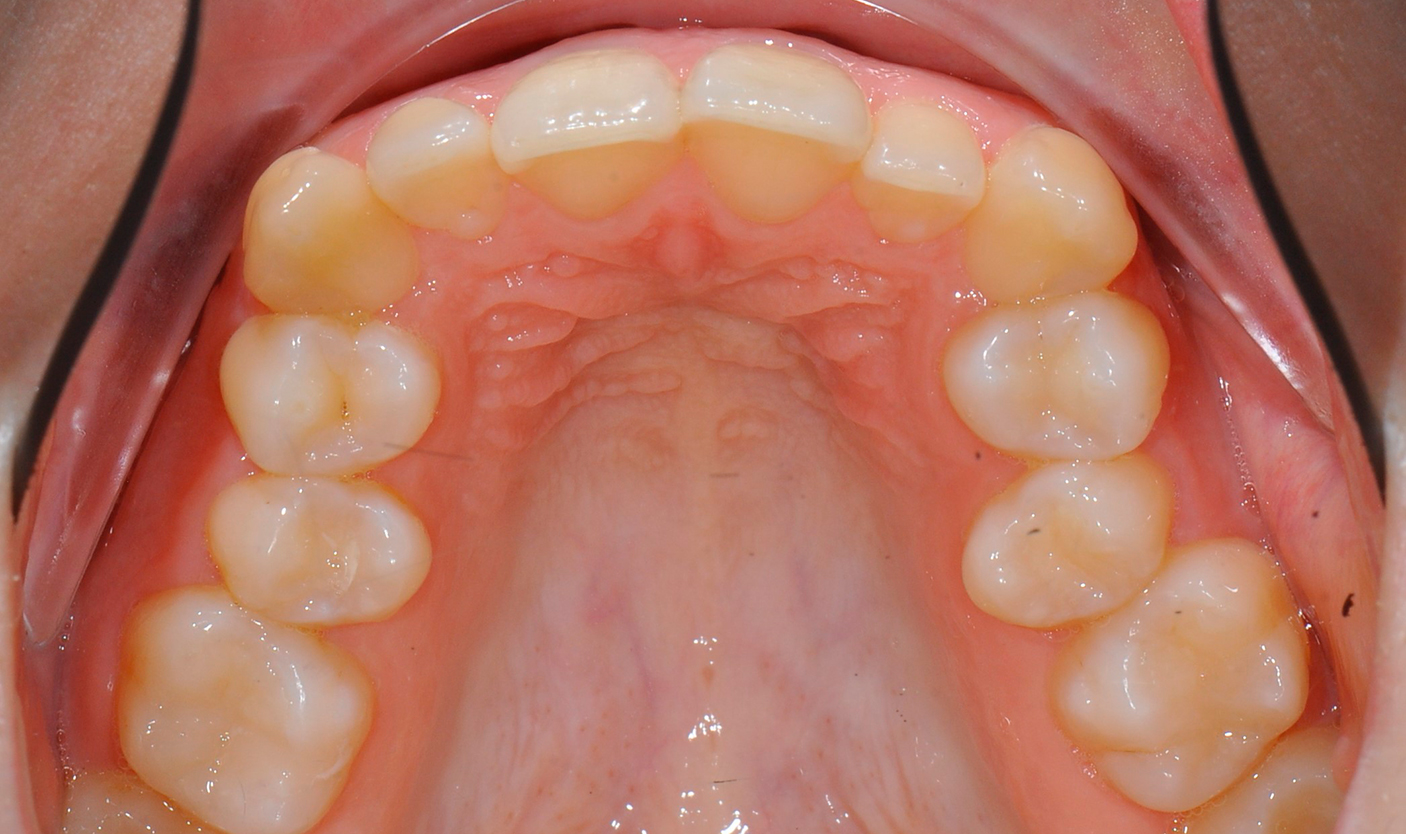

Фото до и после лечения

Наши работы

Фотогалерея